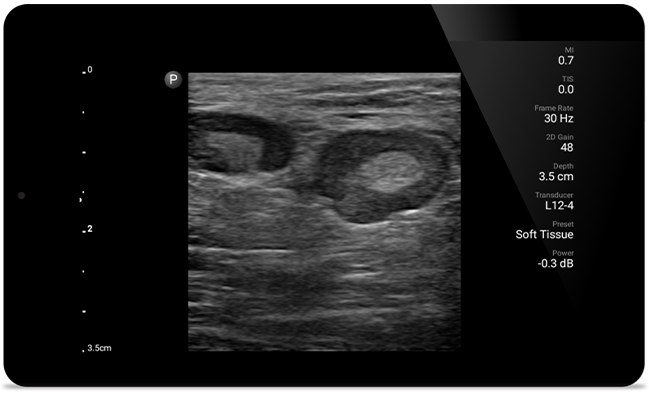

Respond fast with whole-body imagery

Lumify can help you assess patients from head to toe, whether it’s plantar fasciitis, tendonitis or bursitis in the patellar tendon, or even shoulder instability in the rotator cuff.

Get the clarity of larger ultrasound systems with Lumify

SonoCT reinforces real tissue imaging while eliminating random artifacts. This technology produces images superior to conventional imaging in up to 94% of patients.

Lumify transducers for MSK

Lumify L12-4 broadband linear array transducer